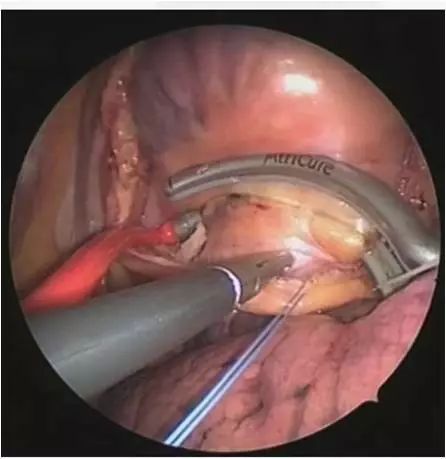

2)外科房颤消融

外科房颤消融术模式图

现阶段,外科房颤消融借助胸腔镜也可以实现微创,尤其适用于心瓣膜疾病合并心房颤动的患者,在指南中,对于需开胸行心脏开放手术的患者,术中行外科消融均为 I 类推荐,且手术成功率60%-70%,不失为房颤治疗的一种方法。

难治性房颤是一个通俗的说法,主要包括:1.经多次导管消融后复发的房颤,发作时间长,至少一年以上,且心超示左房扩大明显(>45mm)的长病程房颤。2.部分发作时间不长,但出现心衰或(和)脑梗并发症的持续性房颤。针对这类病情复杂而心律转复愿望强烈的患者,考虑到转复心律可以极大改善患者的生活质量,而单纯内科或外科消融手术由于存在透壁性和连续性差、无法对阻滞线的完整性进行验证等技术“天花板”,我们采用了内外科杂交治疗手段。内外科杂交治疗,顾名思义是需要心内科和心外科医师联袂进行的一种消融手术。外科医师通过胸腔镜辅助利用微创方法,在左心房外膜面进行消融,而心内科医师则通过导管的方法,在三维标测系统的辅助下在左房的心内膜面进行消融。

房颤杂交手术改变了以往内、外科“单打独斗”的作战模式,实行“多兵种联合作战”,在某种程度上是对房颤治疗理念的一种革新,同时也创建了一种新型的治疗模式。而在杂交手术中,可同时施行左心耳切除,从而在根本上消除了因房颤而导致的血栓形成和卒中风险。从目前我中心杂交手术病人的术后随访(>1年)来看,成功率在80%,是目前治疗难治性房颤最佳且成功率最高的手术方式。